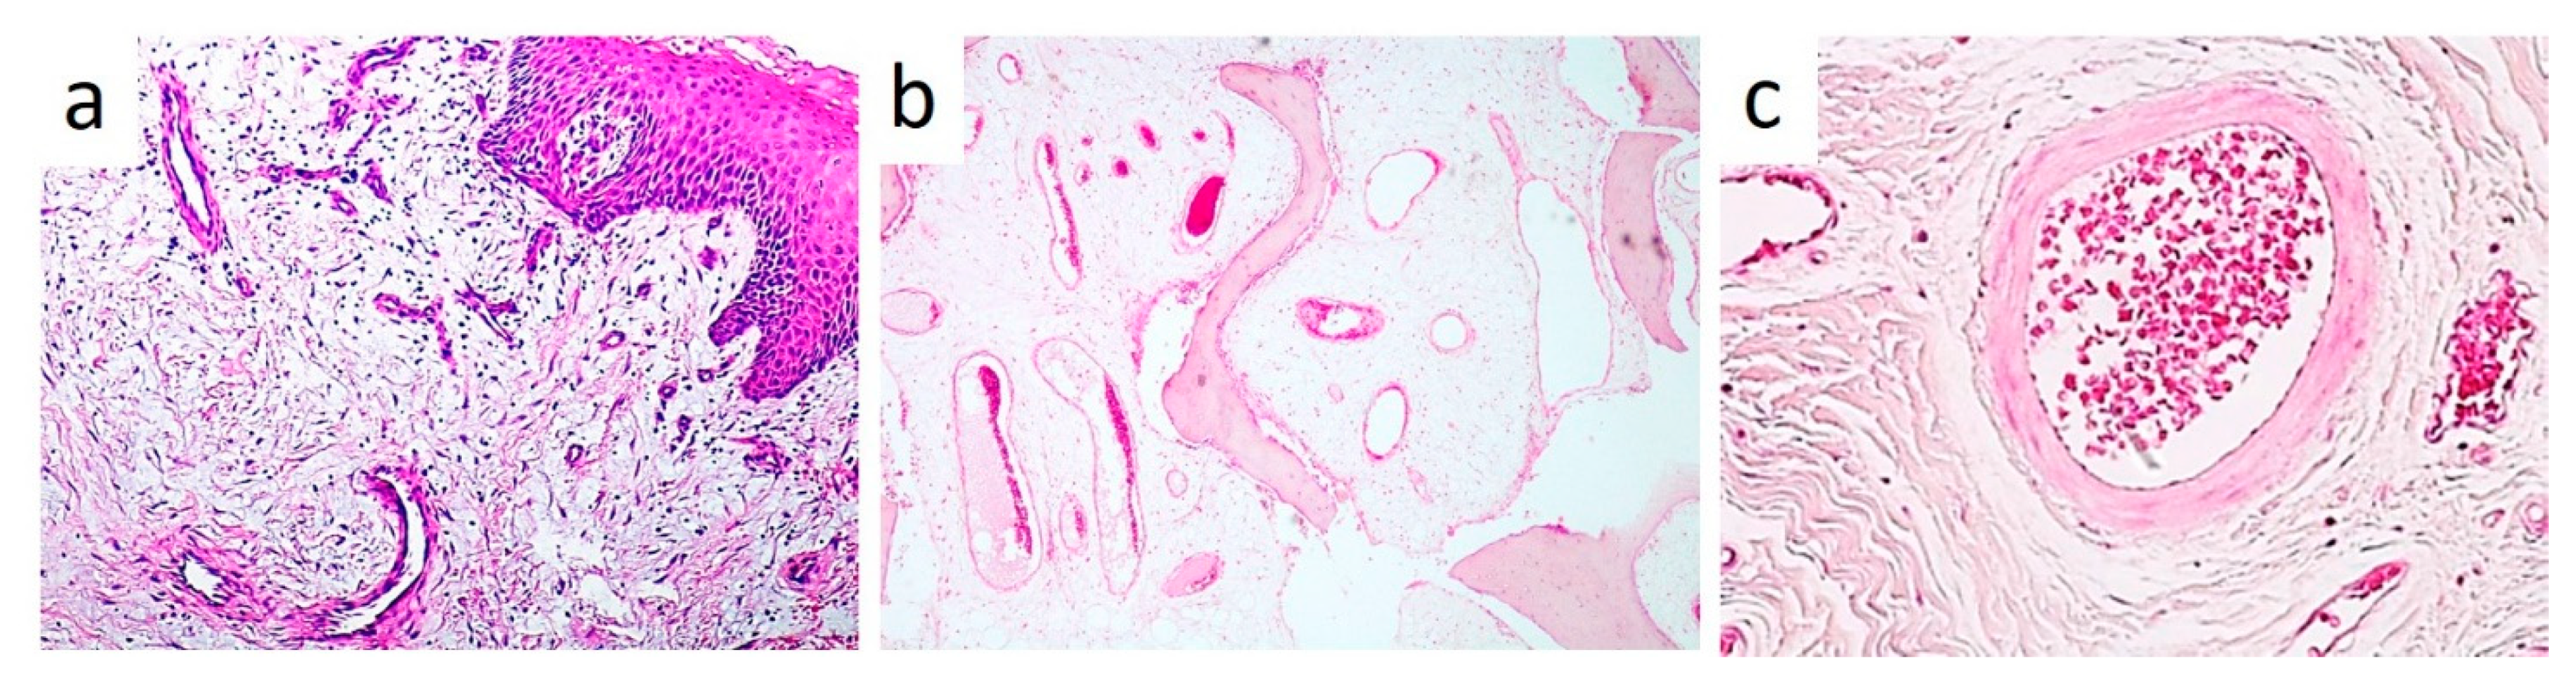

2. Case Presentation